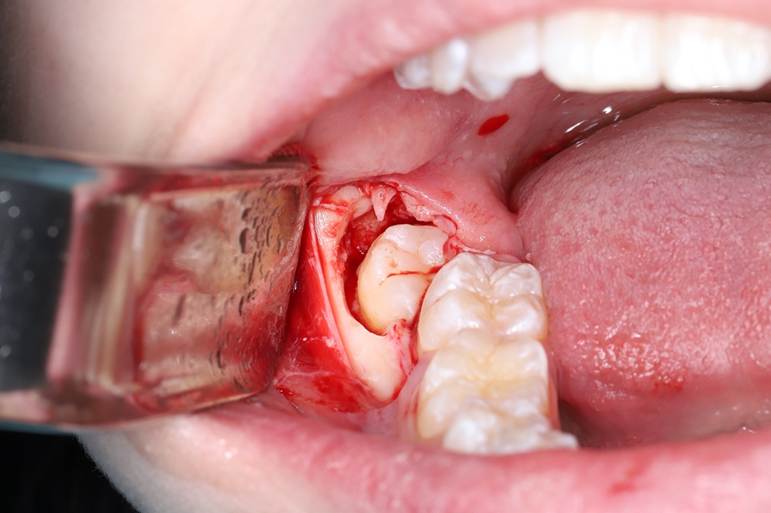

1. Доступ к зубу

Сначала врач делает небольшой надрез десны, чтобы добраться до зуба мудрости.

Это выглядит так